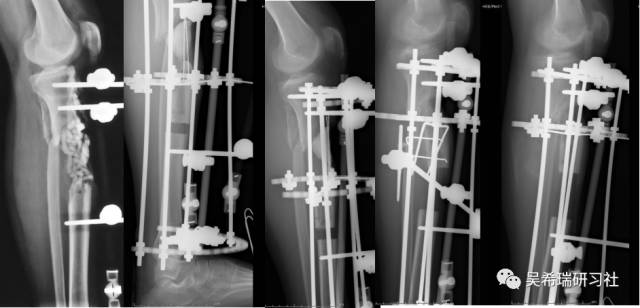

车祸伤多发伤胫骨近端开放骨折软组织缺损右上肢截肢

TIPS:开放骨折外固定游离植皮缩小伤口搬移+半开放植骨半开放植骨=骨水泥技术+开放植骨+骨搬移横向、前后调整搬移骨块下地走路刺激骨愈合早期关节功能锻炼